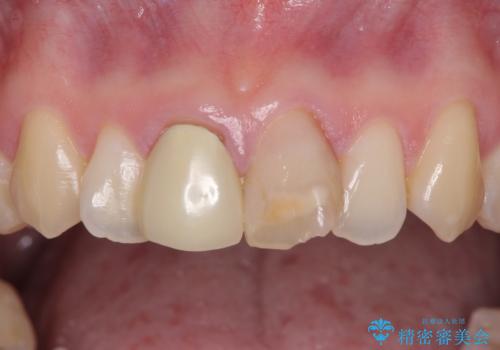

- 前歯の変色が気になるとのことで来院された患者様です。

レントゲン写真より、変色してしまった歯は根管治療がされていなかったため、根管治療後にファイバーコアによる土台築製を行い、前歯2本をオールセラミッククラウンにて補綴することとしました。

変色とともに、捻れていたことも気になっていたので、その両方を解決させることとしました。